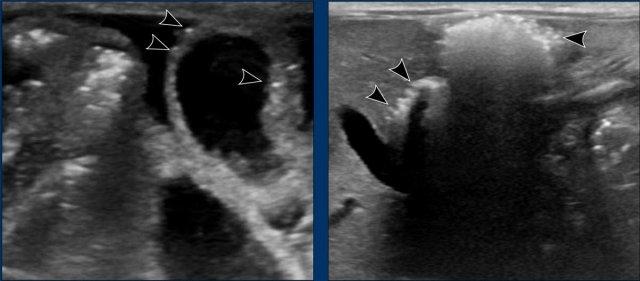

Siêu âm

Siêu âm không chỉ tập trung vào ruột mà còn cần đánh giá sự hiện diện của dịch tự do (*) và khí trong hệ thống tĩnh mạch cửa (mũi tên).

X-quang bụng âm tính không loại trừ được khí trong tĩnh mạch cửa hoặc khí trong thành ruột.

Khí trong tĩnh mạch cửa

Khi khí trong thành ruột được hấp thu vào hệ thống tĩnh mạch và vận chuyển đến tĩnh mạch cửa, bạn có thể thấy các bóng khí viền theo hệ thống tĩnh mạch cửa, gọi là ‘pneumoportogram’.

Khí trong tĩnh mạch cửa lan rộng trên X-quang như trong trường hợp này là khá hiếm gặp.

Siêu âm vượt trội hơn X-quang trong việc phát hiện lượng nhỏ khí trong hệ thống tĩnh mạch cửa.

Các bóng khí có thể được nhìn thấy dưới dạng các đốm tăng âm ở ngoại vi gan, nhưng cũng có thể thấy chúng di chuyển trong tĩnh mạch cửa như được minh họa trong video.